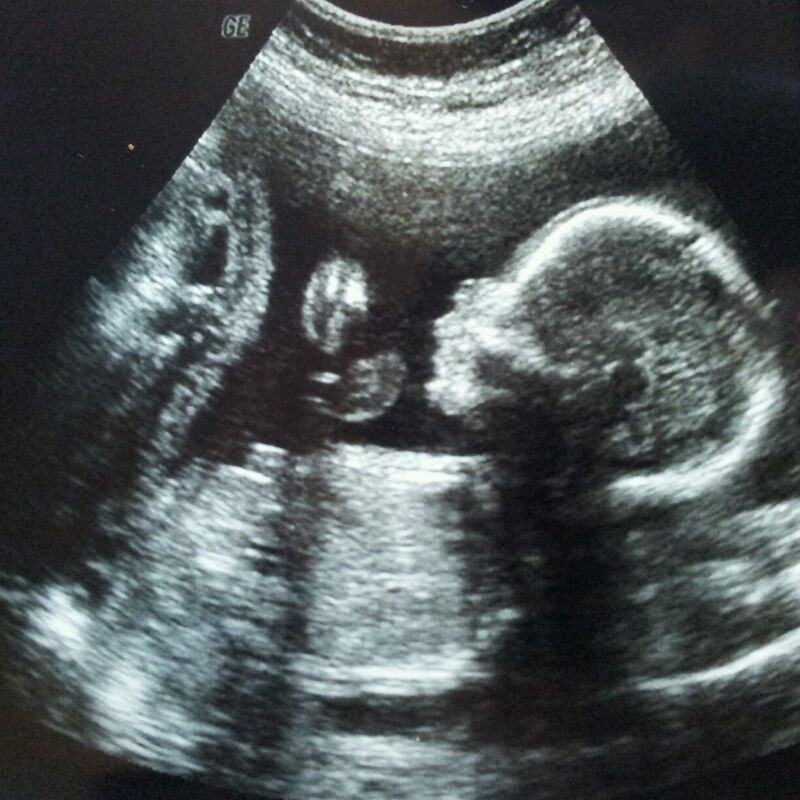

В них, в частности, говорится, что подобные операции приводят к бесплодию, хроническим воспалительным процессам, развитию сердечно-сосудистых заболеваний, раку молочной железы и нервно-психическим расстройствам. А на здоровье будущего ребенка крайне негативно влияют и таблетки для медикаментозного аборта. Ведомство рекомендует пациенткам взвешенно принимать решение о прерывании беременности, а врачам делать женщине УЗИ, чтобы она смогла увидеть малыша и услышать его сердцебиение.

В случае если женщина решила сделать медикаментозный аборт, но передумала при приеме первых таблеток, ей необходимо немедленно обратиться к врачу — тот сделает УЗИ и при наличии сердцебиения плода назначит лечение. При этом, говорится в рекомендациях, таблетки могут повлиять на здоровье будущего ребенка.